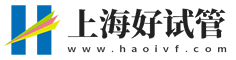

什么是骨肉瘤

一般存在骨肉瘤的患者,肿瘤侵犯骨骼和周围组织,可能需要截肢或保肢手术。即使保留肢体,术后功能也可能受限,对患者的心理和生活质量造成长期影响。

同时骨肉瘤易发生肺部转移,一旦转移,预后极差,5年生存率显著降低。转移可能导致胸痛、咯血等症状,进一步威胁生命。因此出现这类情况,应及时就医排查,早期诊断和综合治疗(如化疗+手术)可显著提高生存率,但需密切关注病情变化。

骨肉瘤早期常表现为持续性疼痛,夜间或活动后加重,随着病情进展,疼痛加剧,可能导致肢体肿胀、活动受限,甚至病理性骨折,严重影响日常生活和运动能力。一般做试管婴儿发现骨肉瘤之后,一定要尽早解决。

尽快前往正规医院的骨科或肿瘤科就诊,进行全面检查,包括影像学检查(如X光、CT、MRI等)和病理活检,以明确诊断和病情分期。